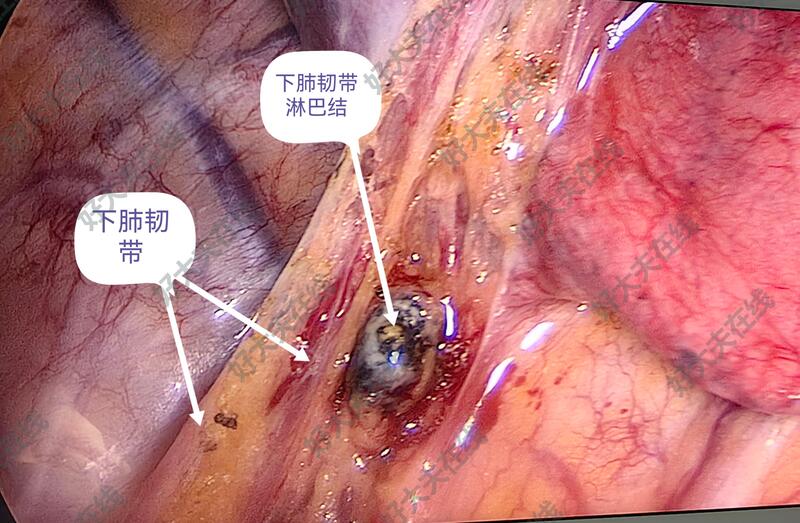

图6-10,男性,74岁,体检发现左肺上叶尖后段结节,亚实性磨玻璃样,毛刺、分叶、胸膜牵拉等,也短期随访,结节不改变,自身和子女的心里压力大(一月内反复不同医院做CT等)。胸腔镜微创手术切除,术中:整个胸膜腔完全闭锁粘连,彻底游离粘连,予以左上肺结节切除,病理报告为良性病变。

治疗中

均胸腔镜微创手术切除,并送病理检查,已经出具病理报告,拔出胸腔闭式引流管,出院。并复查胸片。